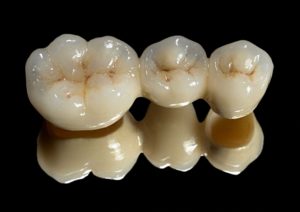

Most ceramiczny na metalu – służy do odbudowy większej ilości zębów, cementowany na stałe.

Most cerconowy wykonany techniką CAD/CAM – służy do odbudowy większej ilości zębów , cementowany na stałe, wykazuje wysoką estetykę , bezmetalowy.

Most cerconowy.